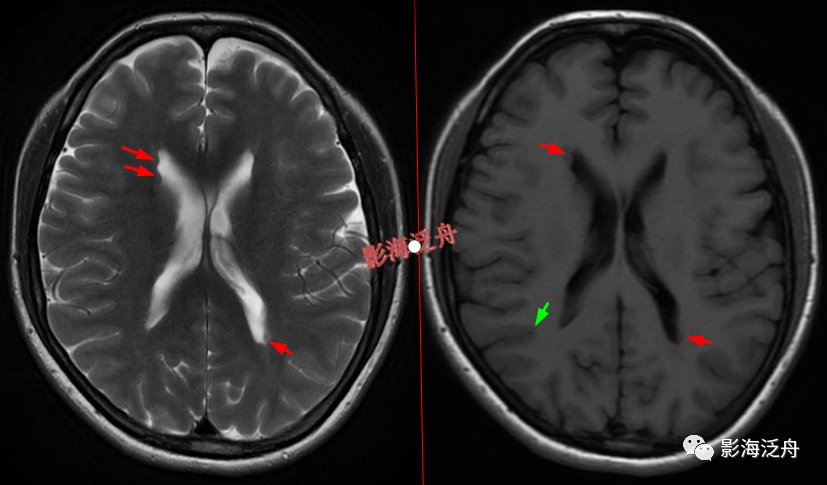

灰质移位,患者既往有癫痫

病史。右侧侧脑室前角及左侧侧脑室后角可见异位的灰质结节(红箭),与大脑皮层下的灰质信号一致(绿箭),灰质异位患者多伴有癫痫症状。